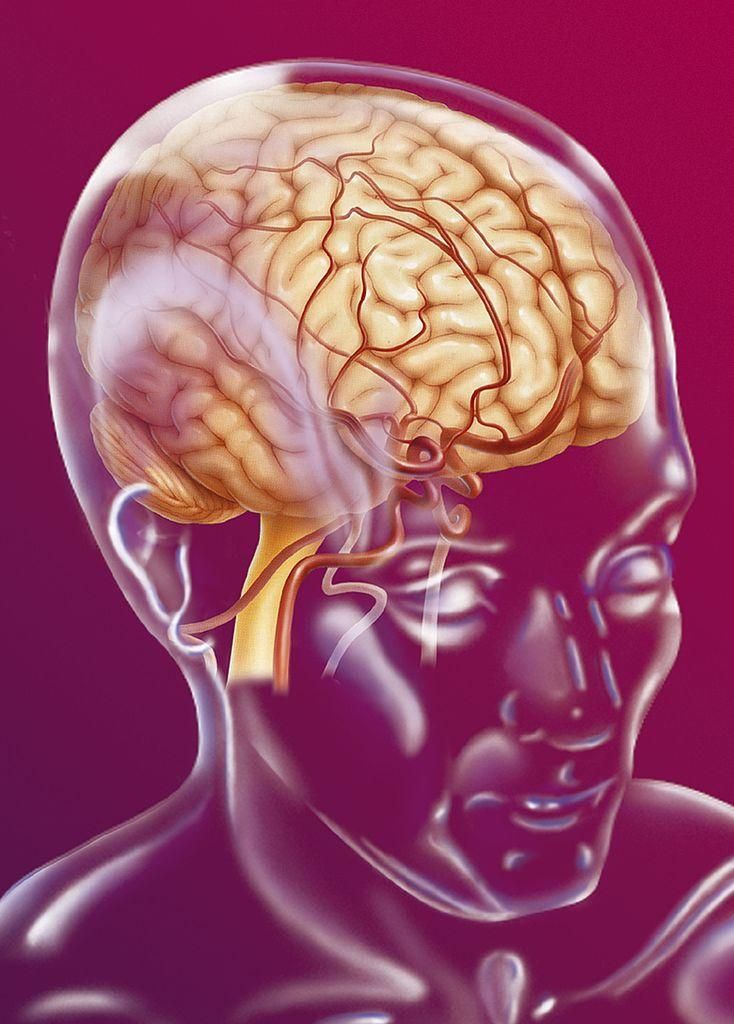

Il cervello è l’organo più complesso e meraviglioso del nostro corpo. Tuttavia, è una struttura misteriosa ed è avvolta da numerosi equivoci e bufale.